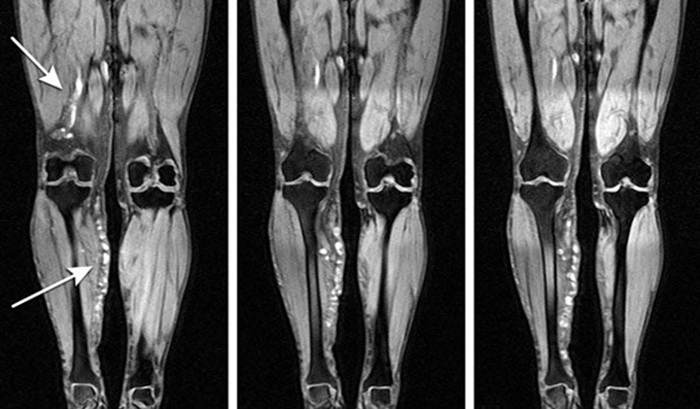

По результатам МР-ангиографии сосудов нижних конечностей получаются черно-белые изображения с очертаниями ног, внутри которых расположены подсвеченные артерии, вены и менее крупные их ответвления. На сканерах высокого разрешения можно различить даже микроскопические капилляры. Кости и соседние мягкие ткани отходят на второй план, ветви кровеносной сети становятся более светлыми и контрастными, что позволяет изучить их строение и найти патологии.

На снимках хорошо видны следующие нарушения:

- аневризмы и стенозы;

- атеросклеротические бляшки;

- доброкачественные гемангиомы;

- злокачественные ангиосаркомы;

- врожденные изменения в строении сосудов;

- недостаточность вен;

- непроходимость артерий в результате закупорки или внешней компрессии;

- воспаления любой природы;

- дегенерация сосудистой стенки;

- нарушение кровотока в результате рубцевания соседних тканей;

- недавние повреждения, разрывы сосудов;

- внутренние кровотечения и гематомы.